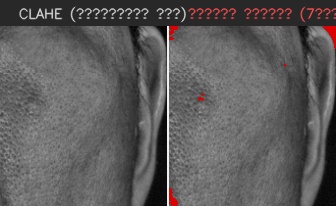

이마

유효 주름 수 4개 · 주 방향 가로

상위 깊이(평균 상위3) 0.320 mm

| # | 길이(mm) | 깊이(mm) | 유효 판정 근거 |

|---|---|---|---|

| 1 | 8.63 | 0.110 | 대표 깊이 0.110 mm가 이 부위 최소 깊이 0.100 mm 이상이고, 유효 길이 8.63 mm가 최소 길이 5.00 mm 이상이어서 노이즈·미세선과 구분되어 유효 주름으로 집계되었습니다. |

| 2 | 10.47 | 0.161 | 대표 깊이 0.161 mm가 이 부위 최소 깊이 0.100 mm 이상이고, 유효 길이 10.47 mm가 최소 길이 5.00 mm 이상이어서 노이즈·미세선과 구분되어 유효 주름으로 집계되었습니다. |

| 3 | 5.76 | 0.322 | 대표 깊이 0.322 mm가 이 부위 최소 깊이 0.100 mm 이상이고, 유효 길이 5.76 mm가 최소 길이 5.00 mm 이상이어서 노이즈·미세선과 구분되어 유효 주름으로 집계되었습니다. |

| 4 | 14.61 | 0.477 | 대표 깊이 0.477 mm가 이 부위 최소 깊이 0.100 mm 이상이고, 유효 길이 14.61 mm가 최소 길이 5.00 mm 이상이어서 노이즈·미세선과 구분되어 유효 주름으로 집계되었습니다. |